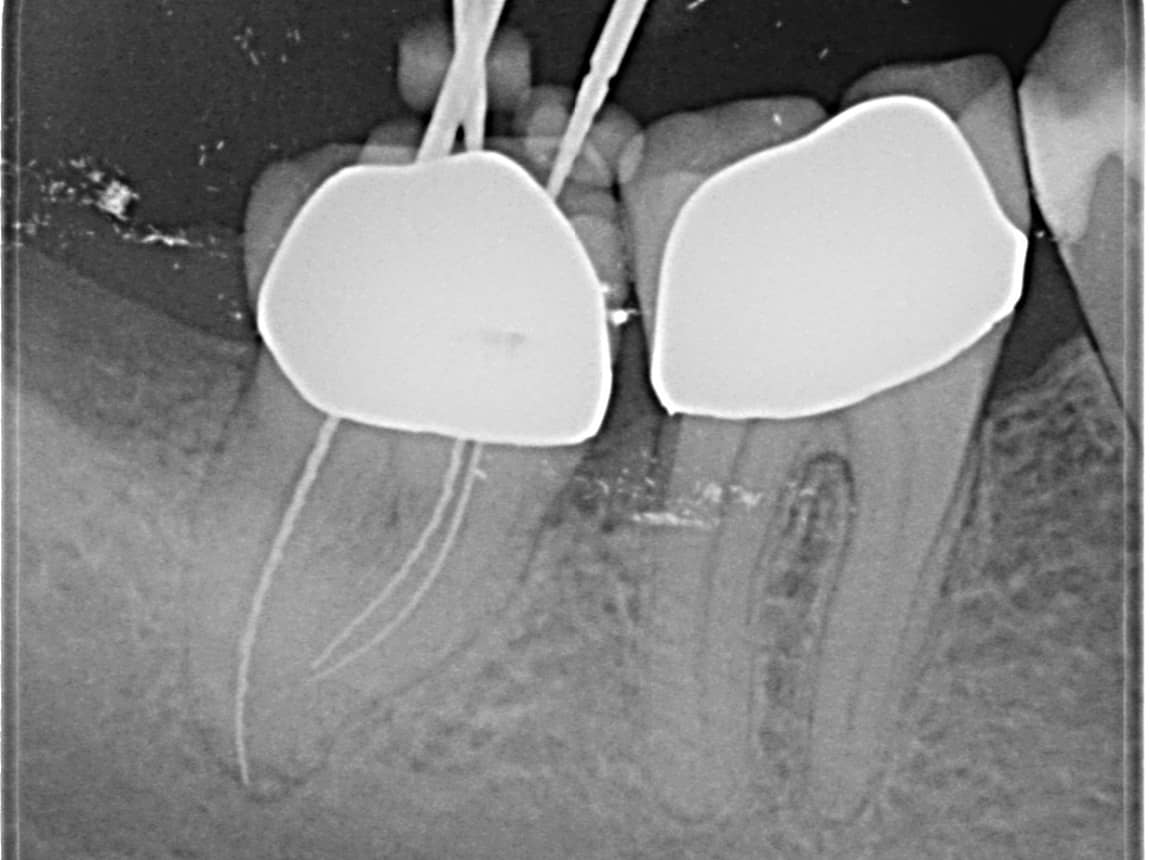

Ist der Defekt zu tief oder der Nerv im Zahn abgestorben, ist vorher eine Wurzelkanalbehandlung notwendig. Dabei wird der Hohlraum im Zahn gesäubert, desinfiziert und anschließend mit Guttapercha versiegelt. Das Ganze erfolgt in unserer Praxis in der Regel mittels moderner maschineller Aufbereitung und durch suffiziente Lokalanästhesie können unnötige Schmerzen verhindert werden.